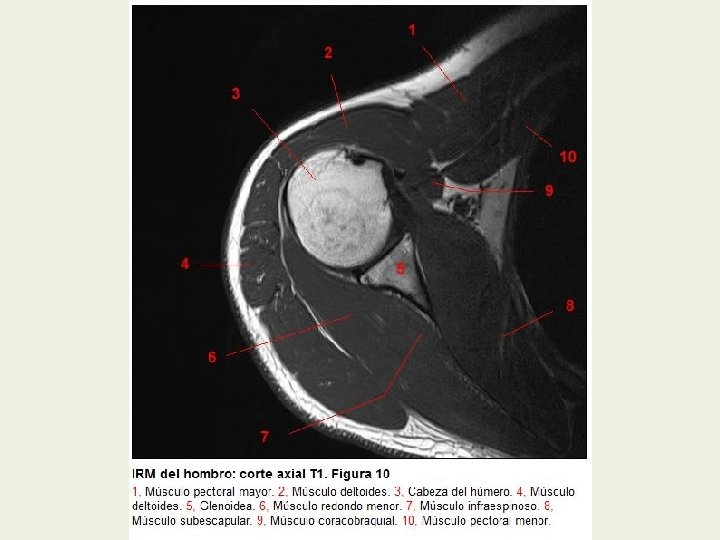

Hombro Cortes axiales RMN